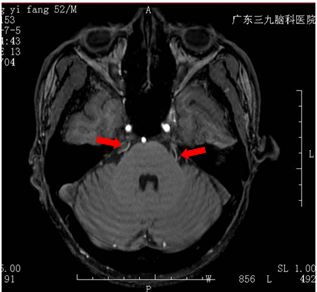

为了进一步治疗自己的疼痛问题,郑先生来到广东三九脑科医院。微侵袭神经外科的医生诊断其为:右侧三叉神经痛,MR检查可见双侧三叉神经颅内段与周围一小血管关系密切。

MR可见双侧三叉神经上骑跨的小血管(箭头所示)